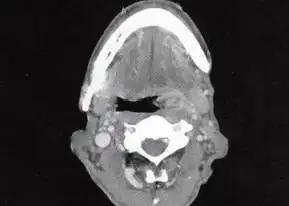

【读片时间】第0623期:扁桃体癌